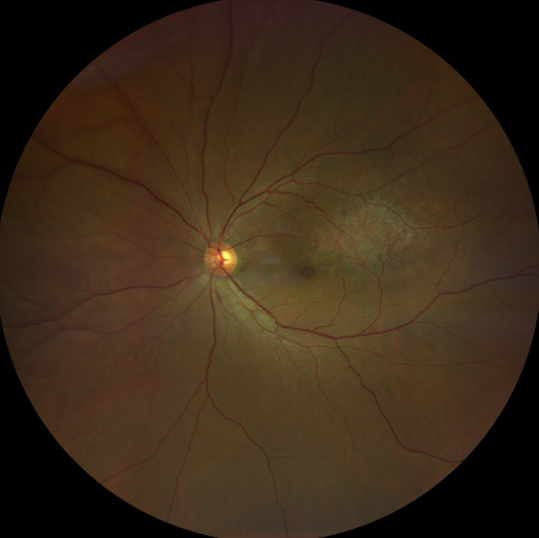

脈絡(luò)膜黑色素瘤是成年人常見的眼內(nèi)惡性腫瘤,其患病率在我國居眼內(nèi)惡性腫瘤的第二位,僅次于視網(wǎng)膜母細胞瘤。其惡性程度高,不僅可致患者喪失視力,而且嚴重威脅患者生命,即使在沒有明確轉(zhuǎn)移前摘除患眼眼球,其5年死亡率也有17%-53%。

脈絡(luò)膜黑色素瘤是葡萄膜惡性腫瘤中較多的一種。葡萄膜腫瘤主要發(fā)生于脈絡(luò)膜、睫狀體和虹膜。其中,脈絡(luò)膜腫瘤占80%,睫狀體腫瘤占12%,虹膜腫瘤占8%。惡性程度高的腫瘤主要發(fā)生于脈絡(luò)膜。發(fā)生于睫狀體的腫瘤惡性程度偏低,發(fā)生于虹膜的腫瘤多數(shù)為良性。脈絡(luò)膜黑色素瘤的特點是惡性程度高、易侵襲轉(zhuǎn)移、預(yù)后極差,嚴重威脅患者的視力和生命。其發(fā)病率有種族差異性,以高加索及白種人居多,黑人發(fā)病率低,亞洲人居于中間。

脈絡(luò)膜黑色素瘤患者在發(fā)病早期無眼痛等癥狀,當腫瘤較小時較難發(fā)現(xiàn),隨著病程進展,腫瘤增大,發(fā)生滲出性視網(wǎng)膜脫離或累及黃斑,視力下降才就診。

脈絡(luò)膜黑色素瘤惡性程度高,50%的患者會發(fā)生轉(zhuǎn)移,轉(zhuǎn)移到肝、肺等遠處臟器,常見的轉(zhuǎn)移方式是經(jīng)鞏膜導管擴散,經(jīng)視神經(jīng)蔓延者罕見。一旦發(fā)生轉(zhuǎn)移,1年生存率只有10%,即絕大多數(shù)病人在半年至1年間會失去生命。因此,早期診斷和選擇合適的治療方式對有效提高局部腫瘤的控制率、降低腫瘤的遠處轉(zhuǎn)移率、延長患者的生存率具有重要意義。